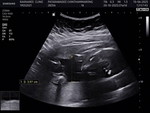

ตอนนี้เเม่ท้อง6เดือนกว่าเคยใช้สิทบัตรทองที่โรงบาลมงกุฏเเจ้งวัฒนะเเล้วก็ย้ายไปใช้สิทโรงพยาบาลแถวๆปทุมถ้าเเม่จะกลับมาใช้สิทที่มงกุฏเเจ้งวัฒนะเราต้องไปติดต่อที่ใหนทำเรื่องกับใครเเล้วก็เตรียมอะไรไปบ้าง